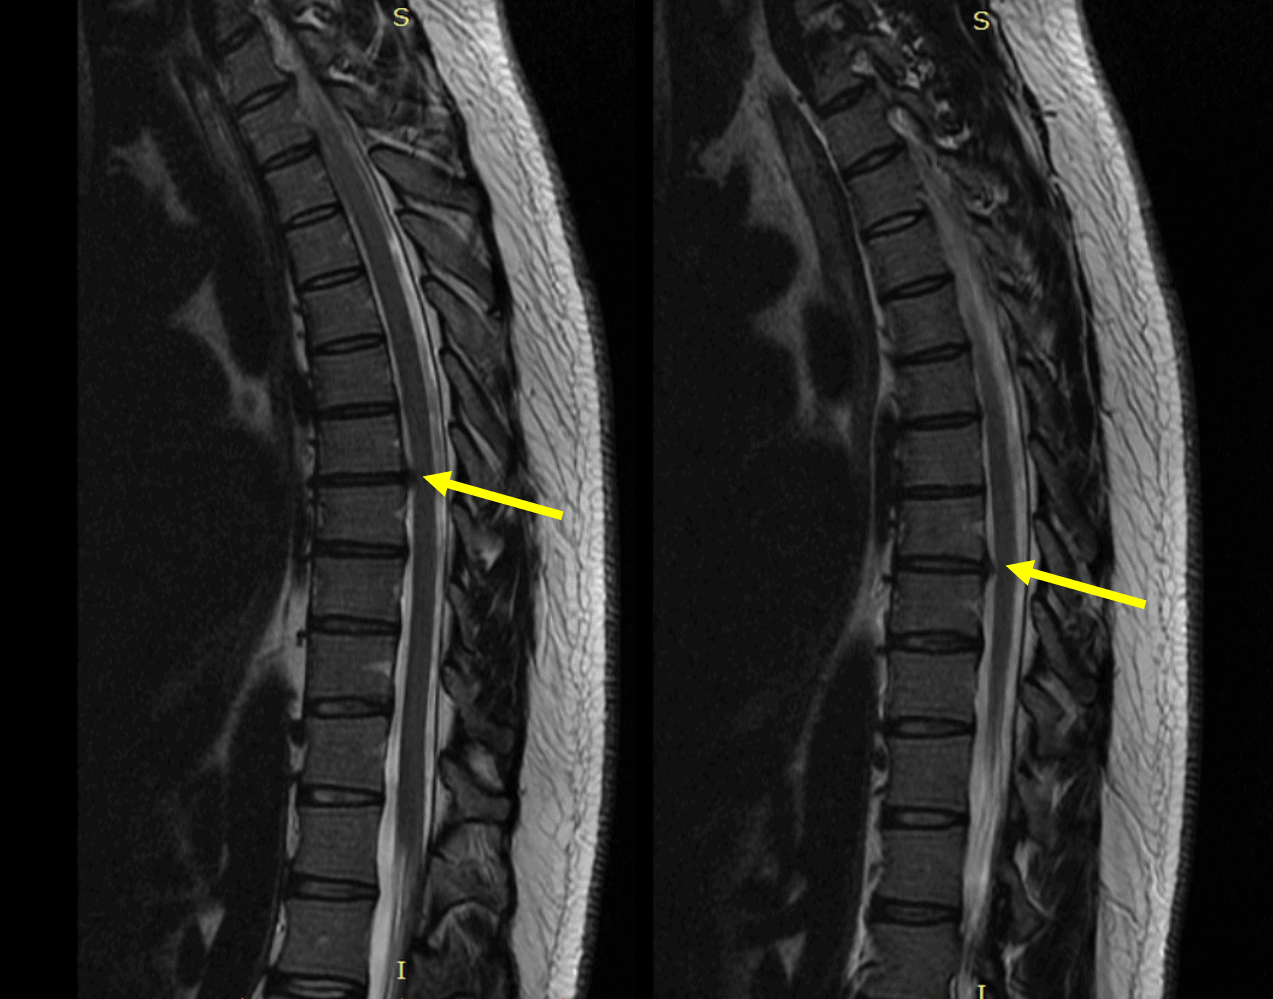

thoracic radiculopathy regenexx bulge injections newer patient